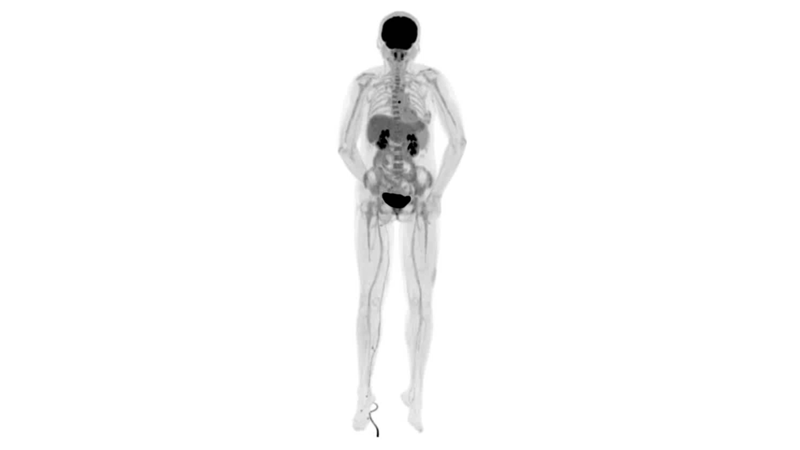

uExplorer探索者不再局限于傳統(tǒng)靜態(tài)代謝過程3D成像,而是在此基礎(chǔ)上新增一個(gè)維度——時(shí)間,從而實(shí)現(xiàn)4D全景成像。

注射總劑量為7.8mCi,14分鐘全身采集時(shí)間,在擁有超高靈敏度與超高分辨率的uEXPLORER上,即可得到展示顯示人體諸多精細(xì)結(jié)構(gòu)的高清三維圖像。

注射總劑量為7.8mCi,注射后1.6小時(shí),基于uEXPLORER探索者掃描1分鐘的圖像

注射總劑量為0.67 mCi FDG(低于常規(guī)劑量的十分之一),基于uEXPLORER探索者掃描15分鐘的圖像

注射總劑量為6.9mCi,注射后10小時(shí),基于uEXPLORER探索者掃描14分鐘的圖像